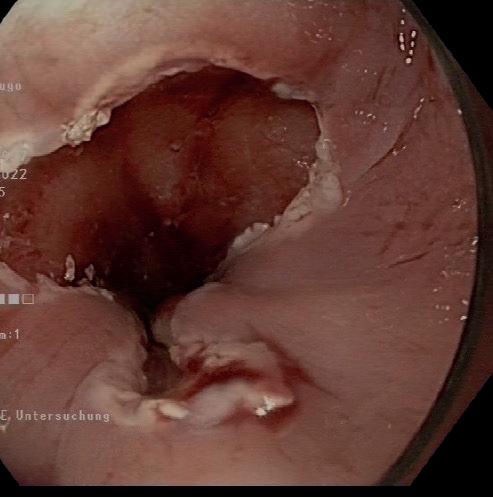

Abb. 1: Barrettmukosa mit Dysplasie

Abb. 2: St.n. Mukosaresektion

Bei Diagnose einer high-grade intraepithelialen Dysplasie (HGIN) und eines Barrettfrühkarzinoms gilt die endoskopi sche Therapie mittlerweile als Standardtherapie. Zwei Ver

fahren ermöglichen die Entfernung von Karzinomvorstufen und Frühkarzinomen: die endoskopische Mukosaresektion (EMR) und endoskopische Mukosadissektion (ESD).

Die zu behandelnde Veränderung wird mit Schlingen (EMR) abgetragen oder mit speziellen Messern (ESD). Bei der ESD können grössere Schleimhautareale als bei der EMR in einem Stück entfernt werden. Diese Technik verbessert die histo pathologische Beurteilbarkeit hinsichtlich der Vollständigkeit der Entfernung, ist aber mit einer höheren Komplikationsrate (Blutung und Perforation) verbunden.